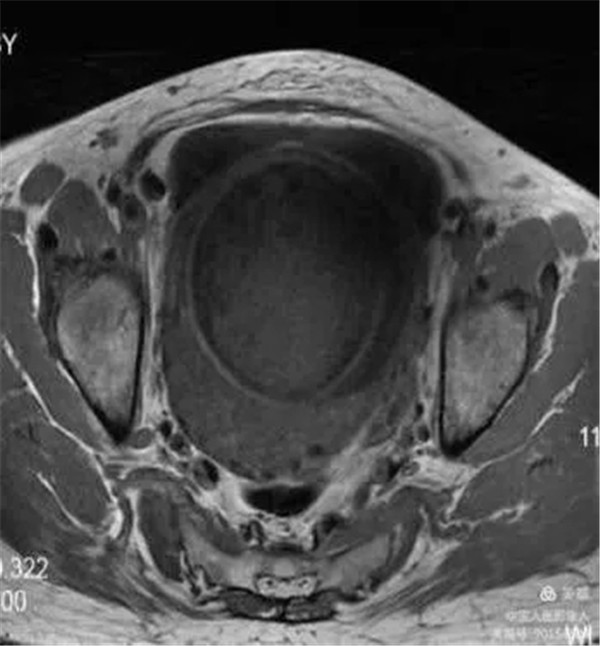

病例11:患者前置胎盘、血管前置、胎盘穿透性植入

图3,轴位T1WI-显示胎盘内信号特点及与周围脂肪间隙境界。